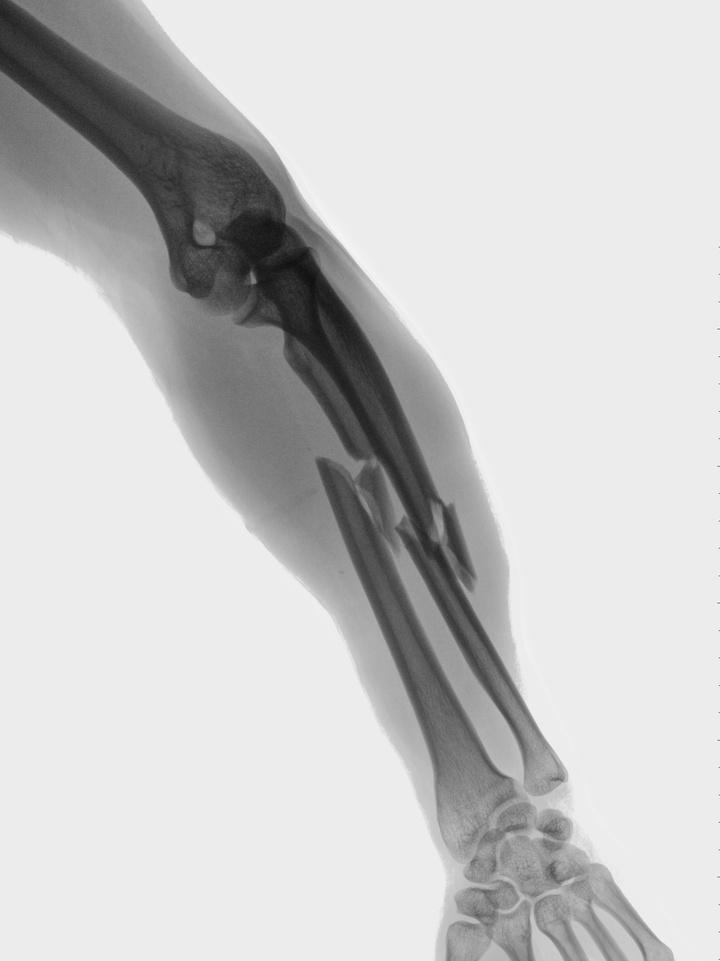

Osteoporosis means "porous" bone and is characterized by either not enough bone formation, excessive bone loss, or a combination of the two.

In osteoporosis, both your bone density and bone quality are reduced which will increase your risk of fracture. Why is this important?

Approximately 10 million Americans have osteoporosis, and another 44 million have low bone density. One in two women and up to one in four men will break a bone in their lifetime due to osteoporosis. For women, the incidence is greater than that of heart attack, stroke, and breast cancer combined.

Six months after a hip fracture, only 15 percent of patients can walk across a room unaided.

Every year, of nearly 300,000 hip fracture patients, one-quarter end up in nursing homes, and half never regain previous function.